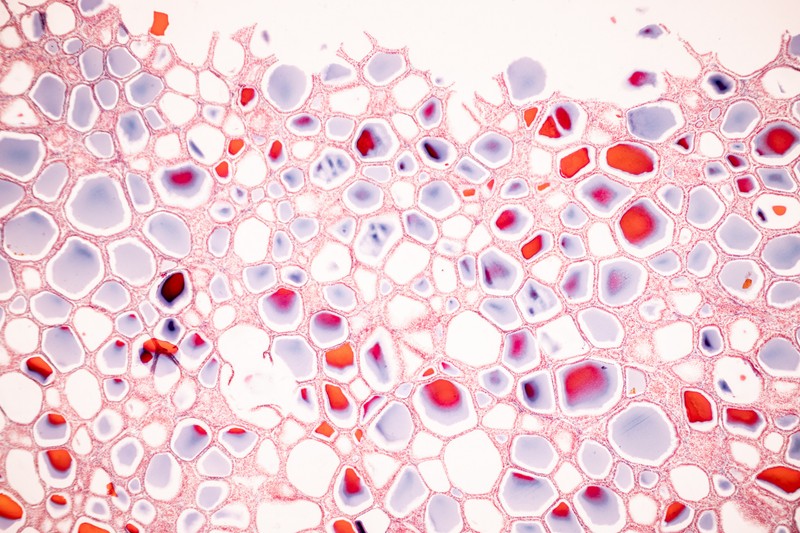

Endokrin mirigyek

Ez az a folyamat, amely a nap minden pillanatában milliónyiszor lezajlik a szervezetében

Amikor ez a preciz folyamat, akár nagyon apró eltéréssel is felborul, máris komoly egészségügyi problémát eredményezhet.